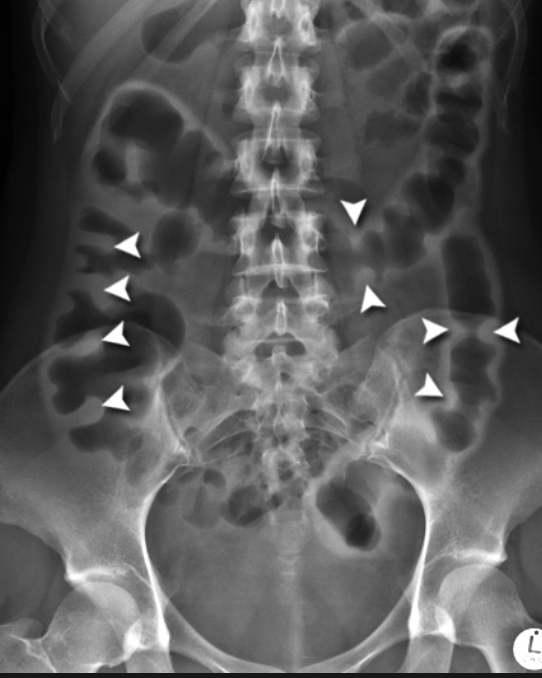

Thumbprinting of the bowel

concerning for severe colitis

ischemic colitis, UC, c. diff, etc